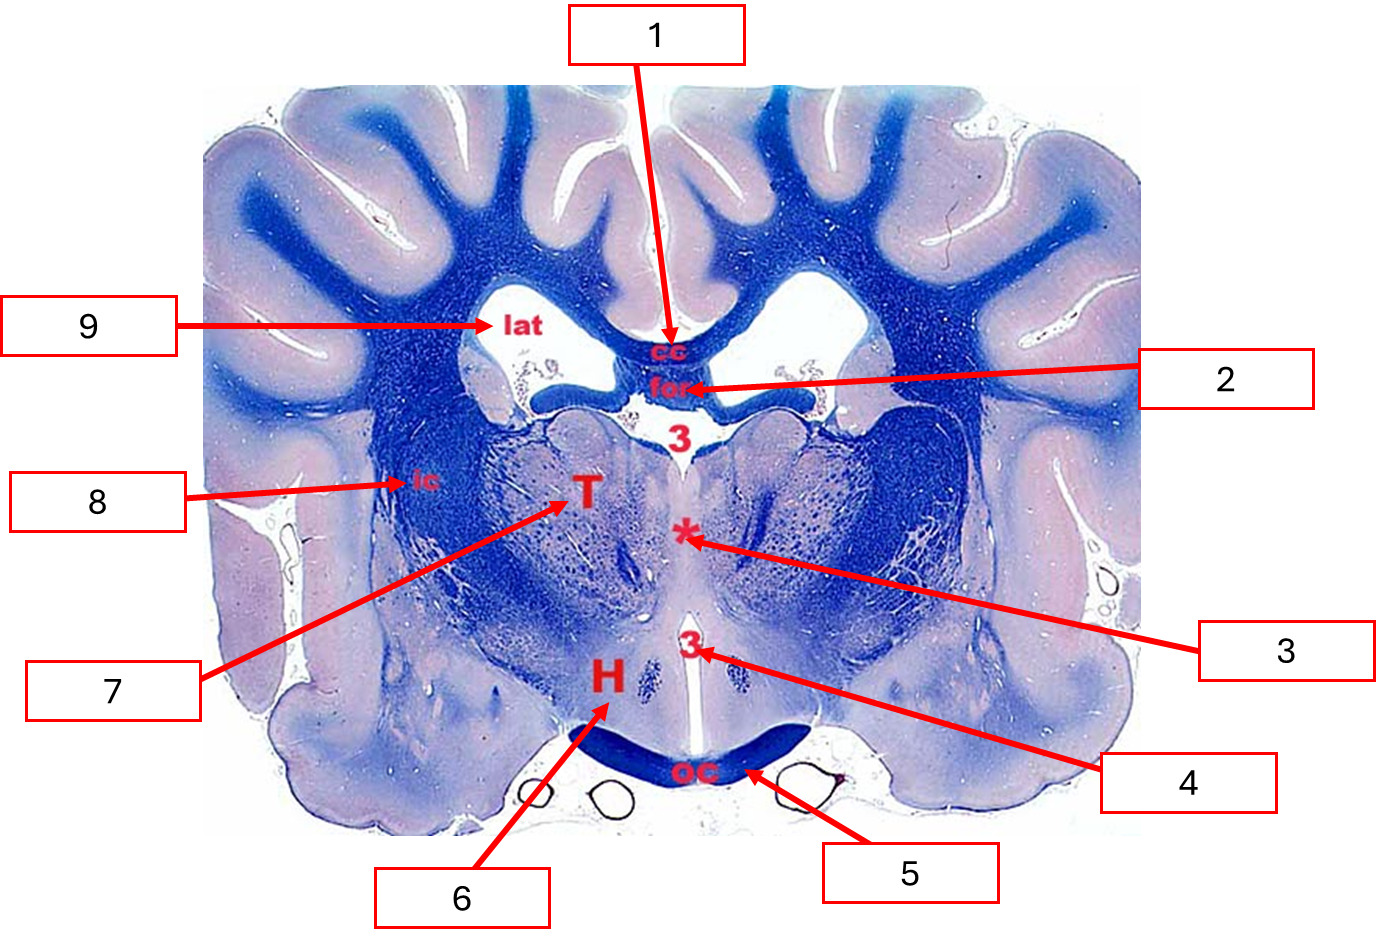

Histo ของ diencephalon

Corpus callosum

Interventricular foramen

Interthalamic adhesion

Third ventricle

Optic chiasm

Hypothalamus

Thalamus

Internal capsule

Lateral ventricle

VENTRICULAR SYSTEM

Mesencephalic aqueduct

Fourth ventricle

Subarachnoid space (เปิดที่ Lateral recess)

Central canal